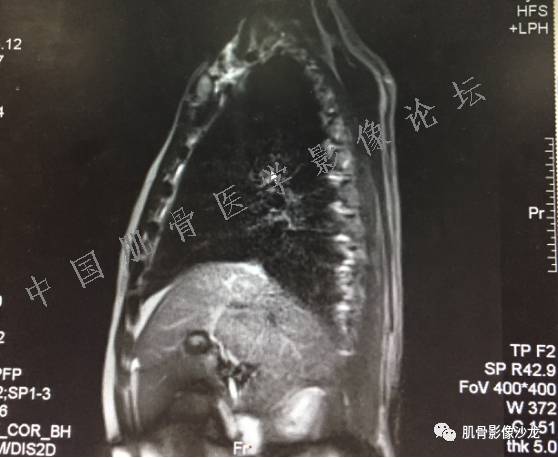

患者于2月前无明显诱因下出现腰骶部疼痛,夜间为重,逐渐加重伴左下肢麻木、疼痛,并有行走活动受限,在我院就诊,摄腰椎及骶髂部CT提示:腰椎骨质退变,腰3-4、4-5椎间盘膨出,骶髂关节炎。自用非甾体抗炎药无好转,再次来院就诊,门诊拟“骶髂关节炎”收住我科。病程无间歇性跛行,大小便正常。

专科检查:神清,脊柱无侧弯后凸畸形,椎体各节段无压、叩痛,双侧棘突旁无压痛,双侧骶髂关节压痛明显,左下肢放射痛,浅感觉较健侧减退,腰椎前屈后伸活动受限,膝、跟腱反射正常。

辅助检查:腰椎及骶髂部CT提示:腰椎骨质退变,腰3-4、4-5椎间盘膨出,骶髂关节炎。